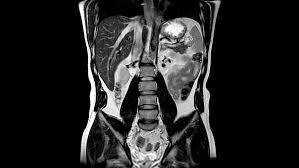

How will you get the test results? The mri of the abdomen will take approximately 60 minutes. What does the procedure involve? In some cases, it may take up to about 2 hours. Abdominal mris are used for a variety of reasons, such as examining:

What do i do after my scan? Newer scanners complete the process in less time. But the magnet is very powerful. In some cases, it may take up to about 2 hours. Do you have to drink anything before a mri scan? Most pelvis mri exams are done in the main hospital, acc or placer clinics. The mri of the abdomen will take approximately 60 minutes. How long to wait after mri? Abdominal mris are used for a variety of reasons, such as examining: How will you get the test results? Please contact the doctor who ordered the test for any test results. What are the risks of an mri of the abdomen? How to prepare for the test:

How long to wait after mri? How long does it take to get mri scan results? Most pelvis mri exams are done in the main hospital, acc or placer clinics. What are the risks of an mri of the abdomen? The mri of the abdomen will take approximately 60 minutes. What does the procedure involve? In some cases, it may take up to about 2 hours. Jul 08, 2017 · preliminary results from an abdominal mri may come within a few days, but comprehensive results can take a week or more.

The doctor who ordered the test will receive the results. Do you have to drink anything before a mri scan? Abdominal mris are used for a variety of reasons, such as examining: May 15, 2021 · an abdominal mri generally takes about 30 to 90 minutes. Most pelvis mri exams are done in the main hospital, acc or placer clinics. There are no known harmful effects from the strong magnetic field used for an mri. Newer scanners complete the process in less time. Please contact the doctor who ordered the test for any test results. The test usually takes 30 to 60 minutes but can take as long as 2 hours. How long until mri scan results come back? Jul 08, 2017 · preliminary results from an abdominal mri may come within a few days, but comprehensive results can take a week or more. What does the procedure involve? How to prepare for the test: